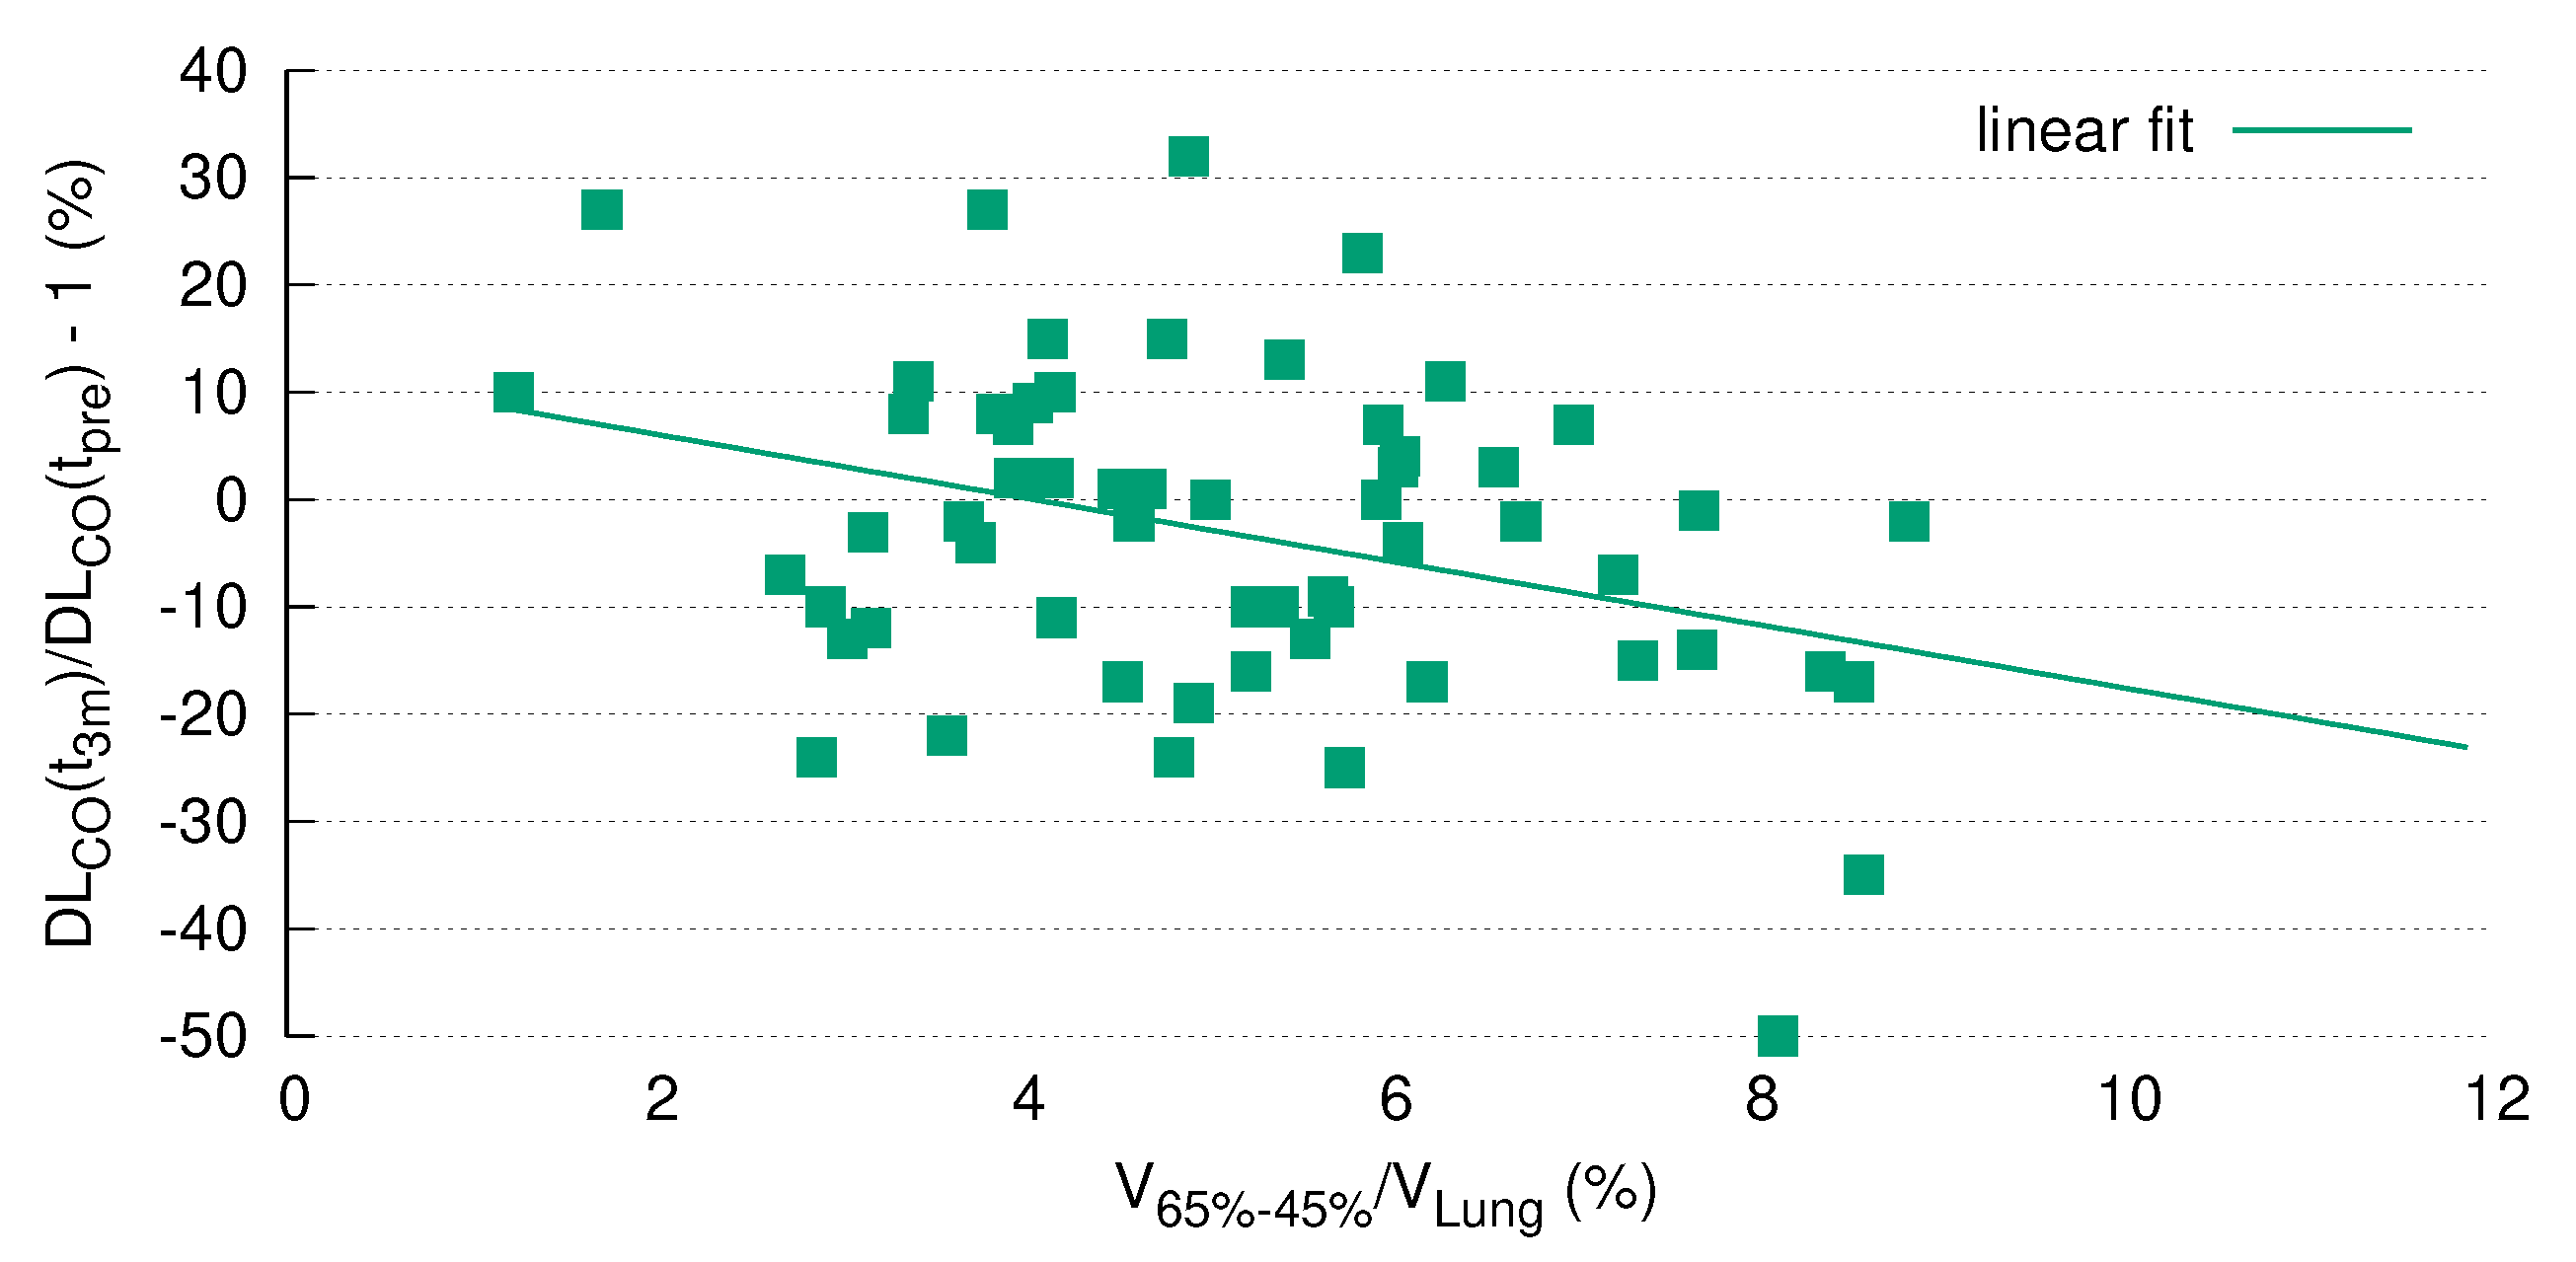

3.5. DL Correlates with V

3.7. DL after RT Is Predicted by V

4. Discussion